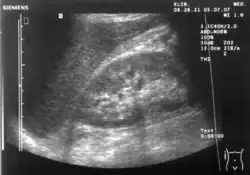

A normal ultrasonographic view of Morison's pouch. The bright line is the capsule of the kidney; there is no fluid present and hence no visible space. -